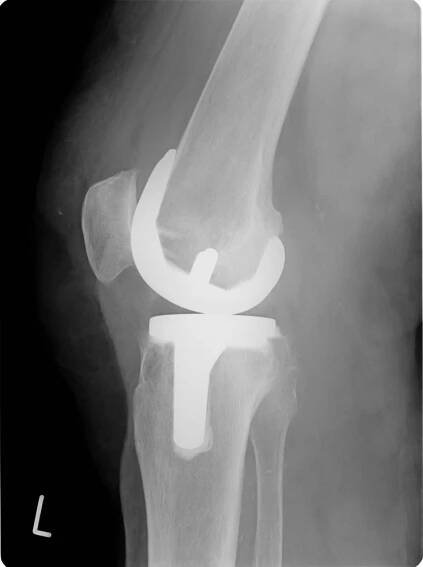

Obr. 4a: RTG obraz náhrady kolenního kloubu